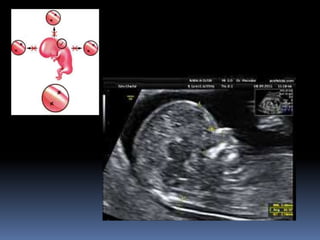

Corazón inicia latidos a las

5 semanas de gestación